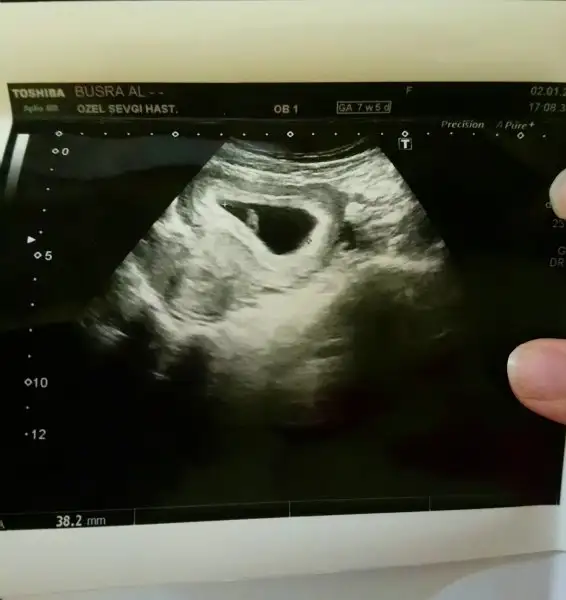

Bana tahmin yapmamissiniz bende tahmin istiyorum (karından USG)